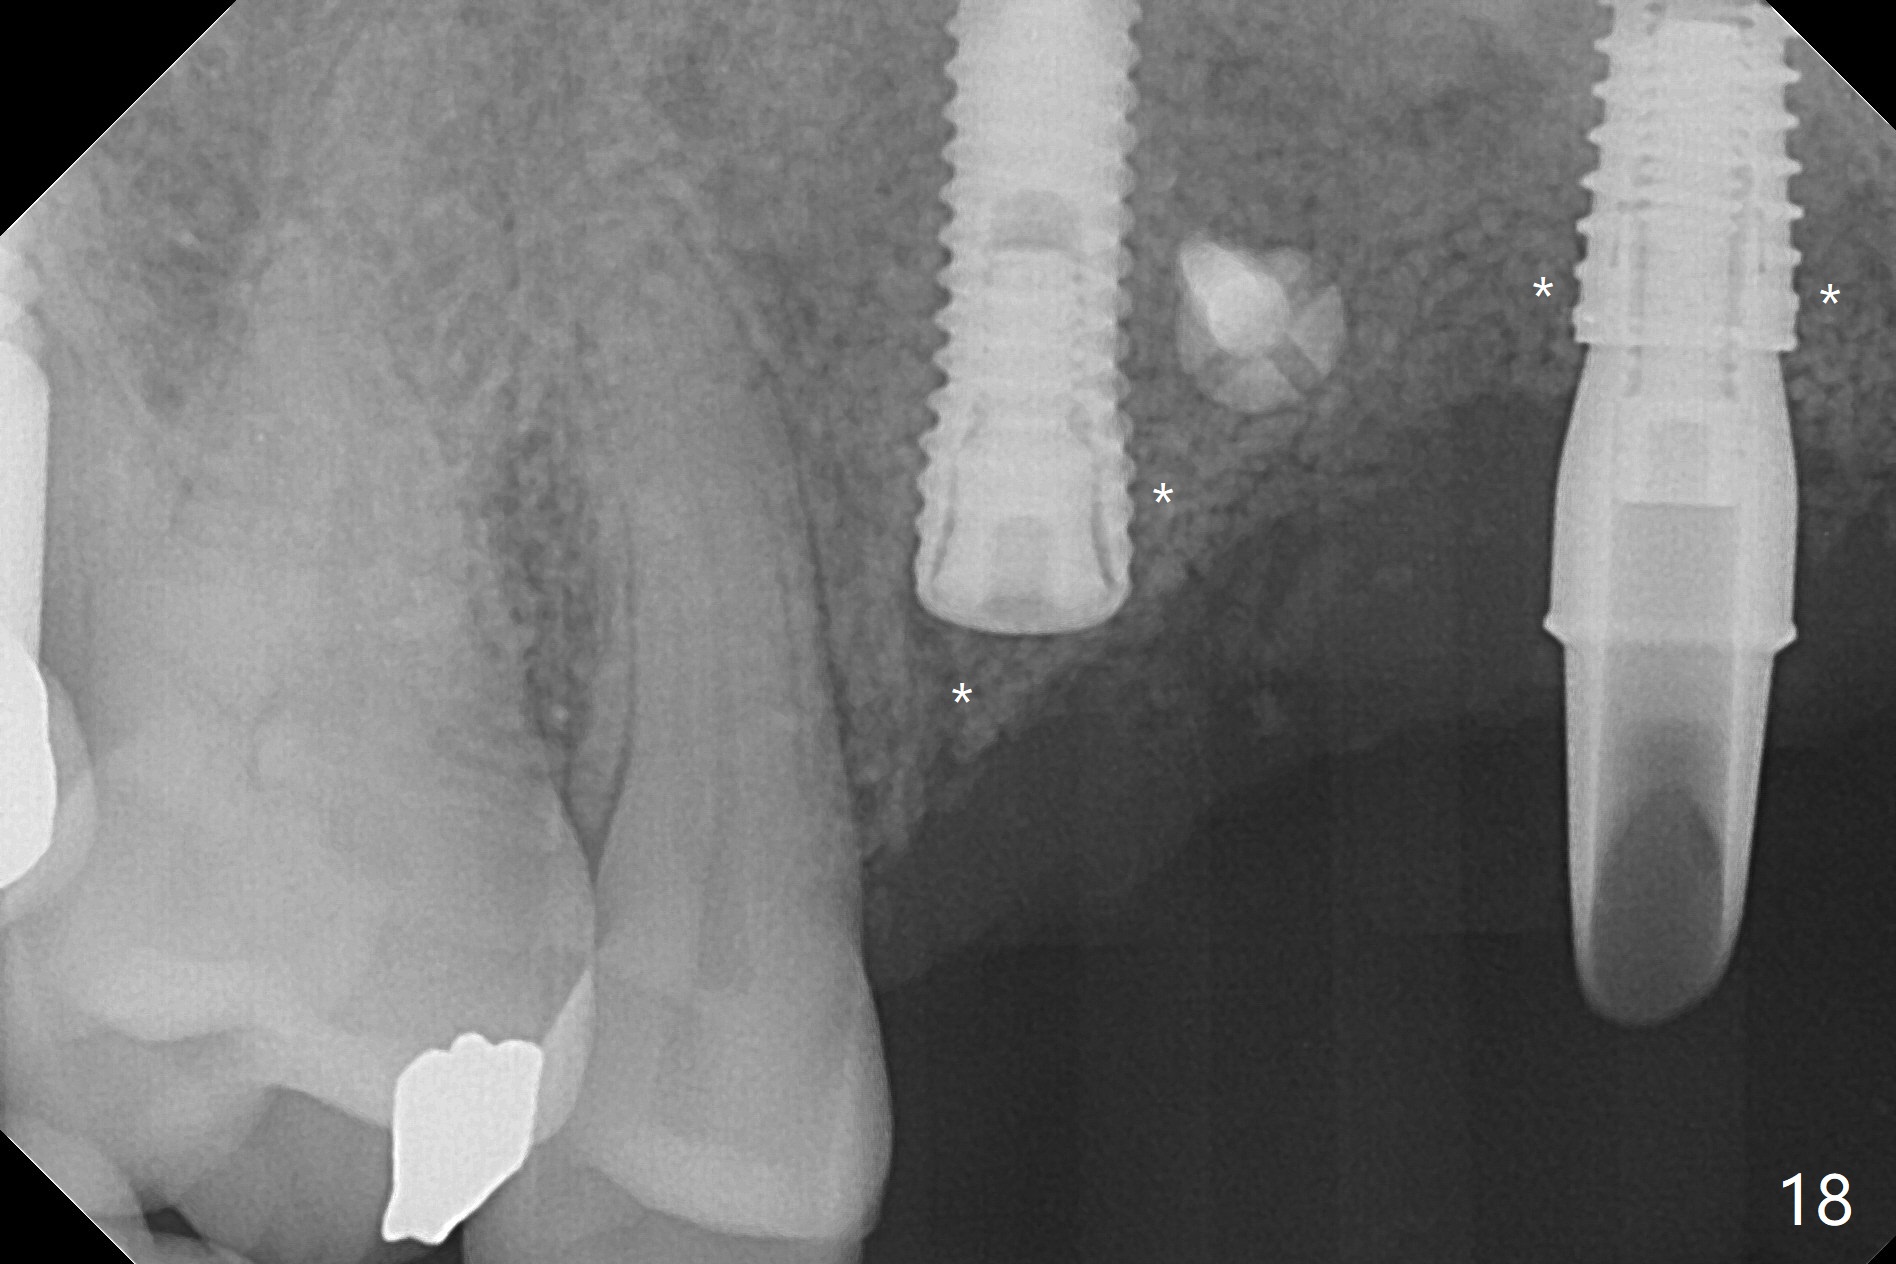

在6,7号牙位牙槽嵴切口,翻瓣,找不到上次放置的tenting screw,不过7号牙位骨质虽然低,够宽的,开始钻洞(图四),植入3.8乘8.5毫米植体,扭力足够(图五),近中舌侧暴露螺纹堆加骨粉(图五*),然后放置基台,再次在后者周围放置骨粉(图五至七),覆盖两张PRF膜后缝合(图八),最后在三个箭头周围放置牙周敷料。术后CT显示植体与tenting screws(图九,十箭头)有一定距离,但是5号牙植体颊侧根尖穿孔(图九 *)。如果植体不脱落,需做侧方切口植骨。术后七天7号植体腭侧肿胀(图十一 *),切开没有脓水,插入牙胶尖,它末端指向7号植体周围tenting screw。后者可能需要拔除,同时5号牙颊侧根尖植骨,但是为时太早,可能打搅骨粉生长。术后两周腭侧肿胀没有消失,但是不痛,继续观察。术后接近6个月,软组织正常(图十三),但是5,7植体周围没有骨质(图十四,五)。由于近中tenting screws周围软组织触痛(局麻不全情况下),螺钉取出(图十六,七(*)),而远中螺钉好像有帮助5植体螺纹骨粉撑起,所以留下(腭侧穿孔部分去除),最后放置粘性骨粉(图十八:*)和PRF膜(两张由7基台打孔固定)。